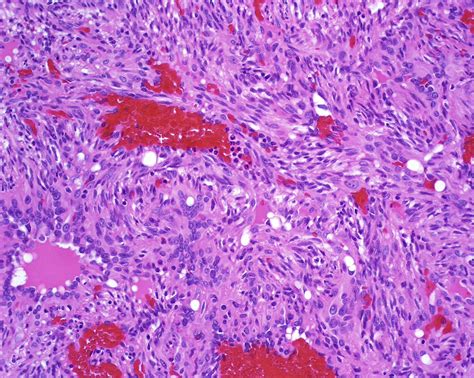

Spindle cell tumors are a diverse group of neoplasms characterized by spindle-shaped cells. These tumors can arise in various tissues and organs throughout the body, making their diagnosis and treatment a complex process. Understanding the different types, causes, symptoms, and treatment options for spindle cell tumors is crucial for both healthcare professionals and patients.

Spindle cell tumors are named for their distinctive spindle-shaped cells, which are elongated and tapered at both ends. These tumors can be benign or malignant, and their behavior can vary widely depending on the specific type and location. Some common types of spindle cell tumors include: